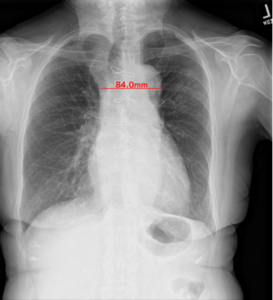

[2]心胸郭比(CTR:Cardio-Thoracic Ratio)の計測

肺野の最大幅に対する心臓の最大幅の比[%]を算出し,計測結果が基準値を超えた場合に表示する。

<心胸郭比の拡大について>

心胸郭比は,胸部X線画像での心臓の幅と胸郭の幅の比率。心陰影の拡大が見られる場合には心不全が疑われ,特に救急現場における心不全の診断に,胸部X線画像は有用であると言われている(5)。

EIRL Chest Screeningによる心胸郭比の計測結果の表示例